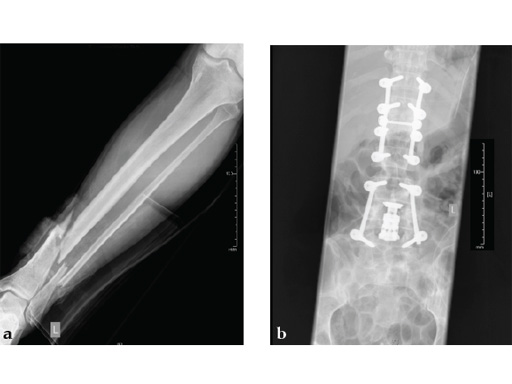

Case 2: Grade II open distal tibial fracture in a polytraumatized 52-year-old man.